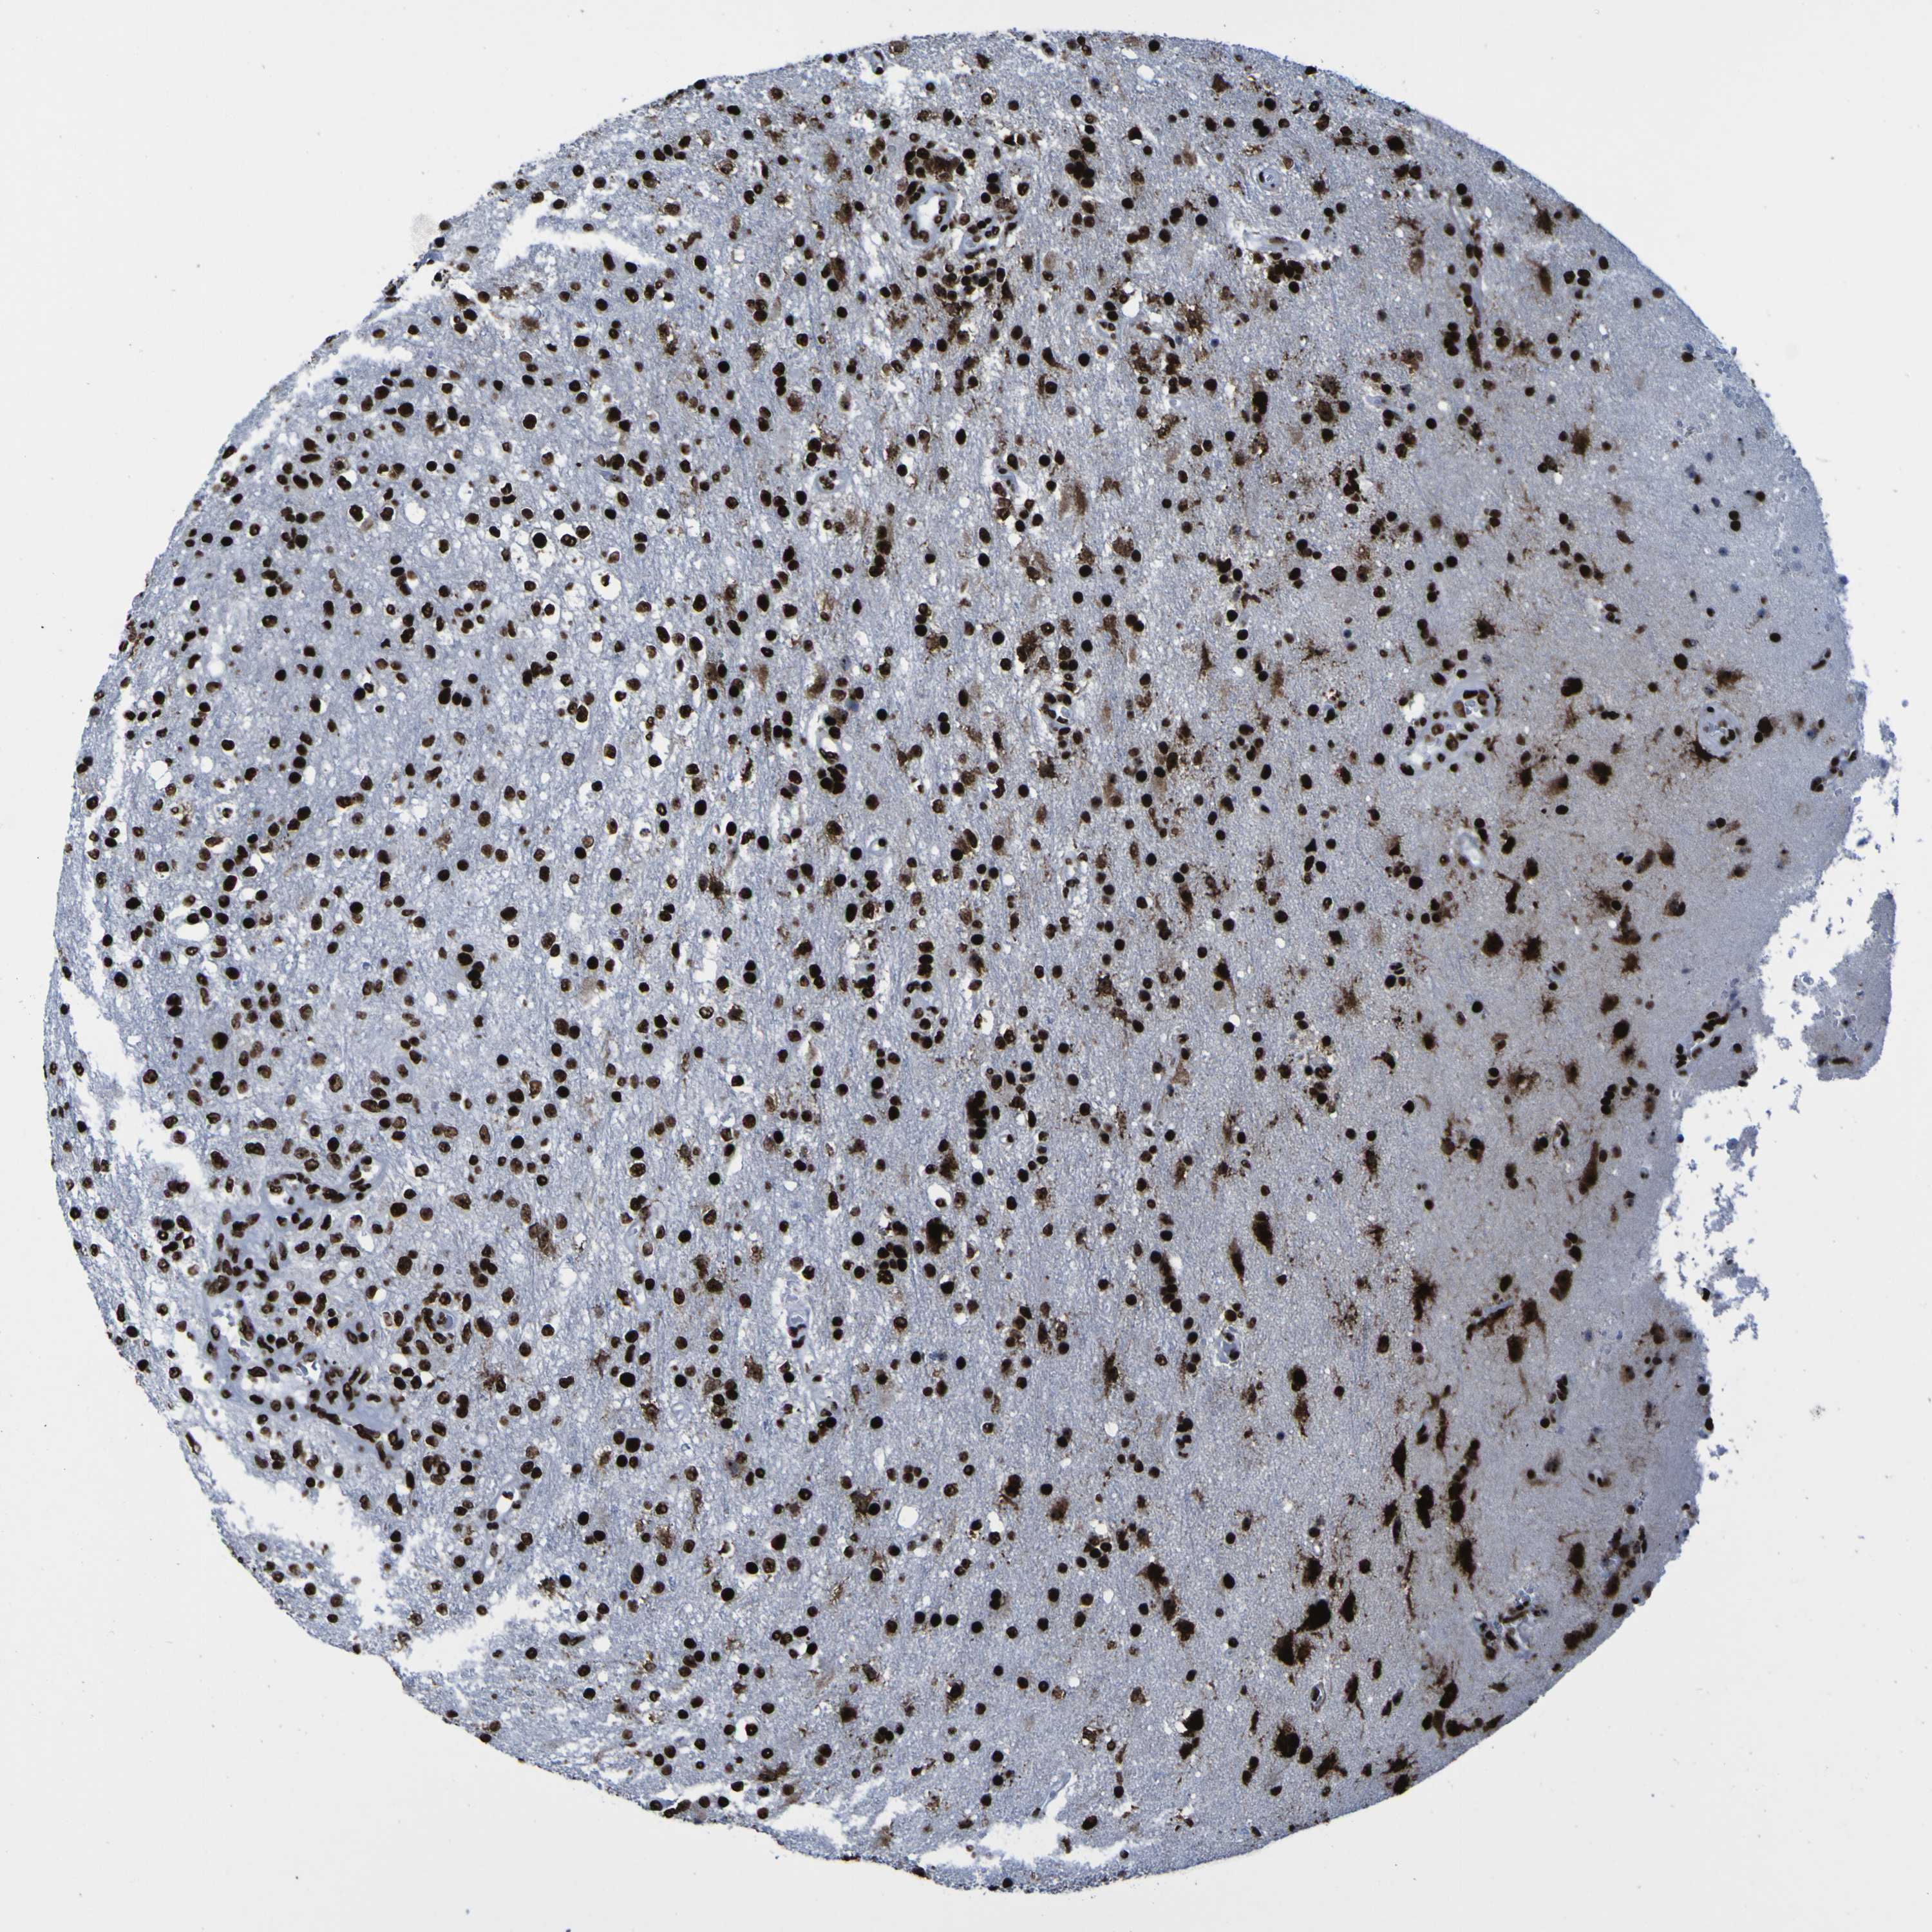

GLIOMA - Protein expressioni

A mouse-over function shows sample information and annotation data. Click on an image to view it in a full screen mode. Samples can be filtered based on level of antibody staining by selecting one or several of the following categories: high, medium, low and not detected. The assay and annotation is described here.

Note that samples used for immunohistochemistry by the Human Protein Atlas do not correspond to samples in the TCGA dataset.

Antibody stainingi

Antibody staining in the annotated cell types in the current human tissue is reported as not detected, low, medium, or high, based on conventional immunohistochemistry profiling in selected tissues. This score is based on the combination of the staining intensity and fraction of stained cells.

Each image is clickable and will lead to virtual microscopy that enables deeper exploration of all samples and also displays staining intensity scores, fraction scores and subcellular localization as well as patient and tissue information for each sample.

Antibody HPA011384

Antibody CAB012983

Staining

High

Medium

Low

Not detected

Intensity

Strong

Moderate

Weak

Negative

Quantity

>75%

75%-25%

<25%

None

Location

Nuclear

Cytoplasmic/membranous

Cytoplasmic/membranous,nuclear

Glioma, malignant, High grade

Glioma, malignant, Low grade